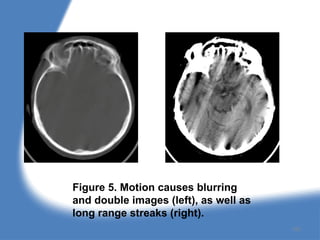

Figure 5. Motion causes blurring

and double images (left), as well as

long range streaks (right).